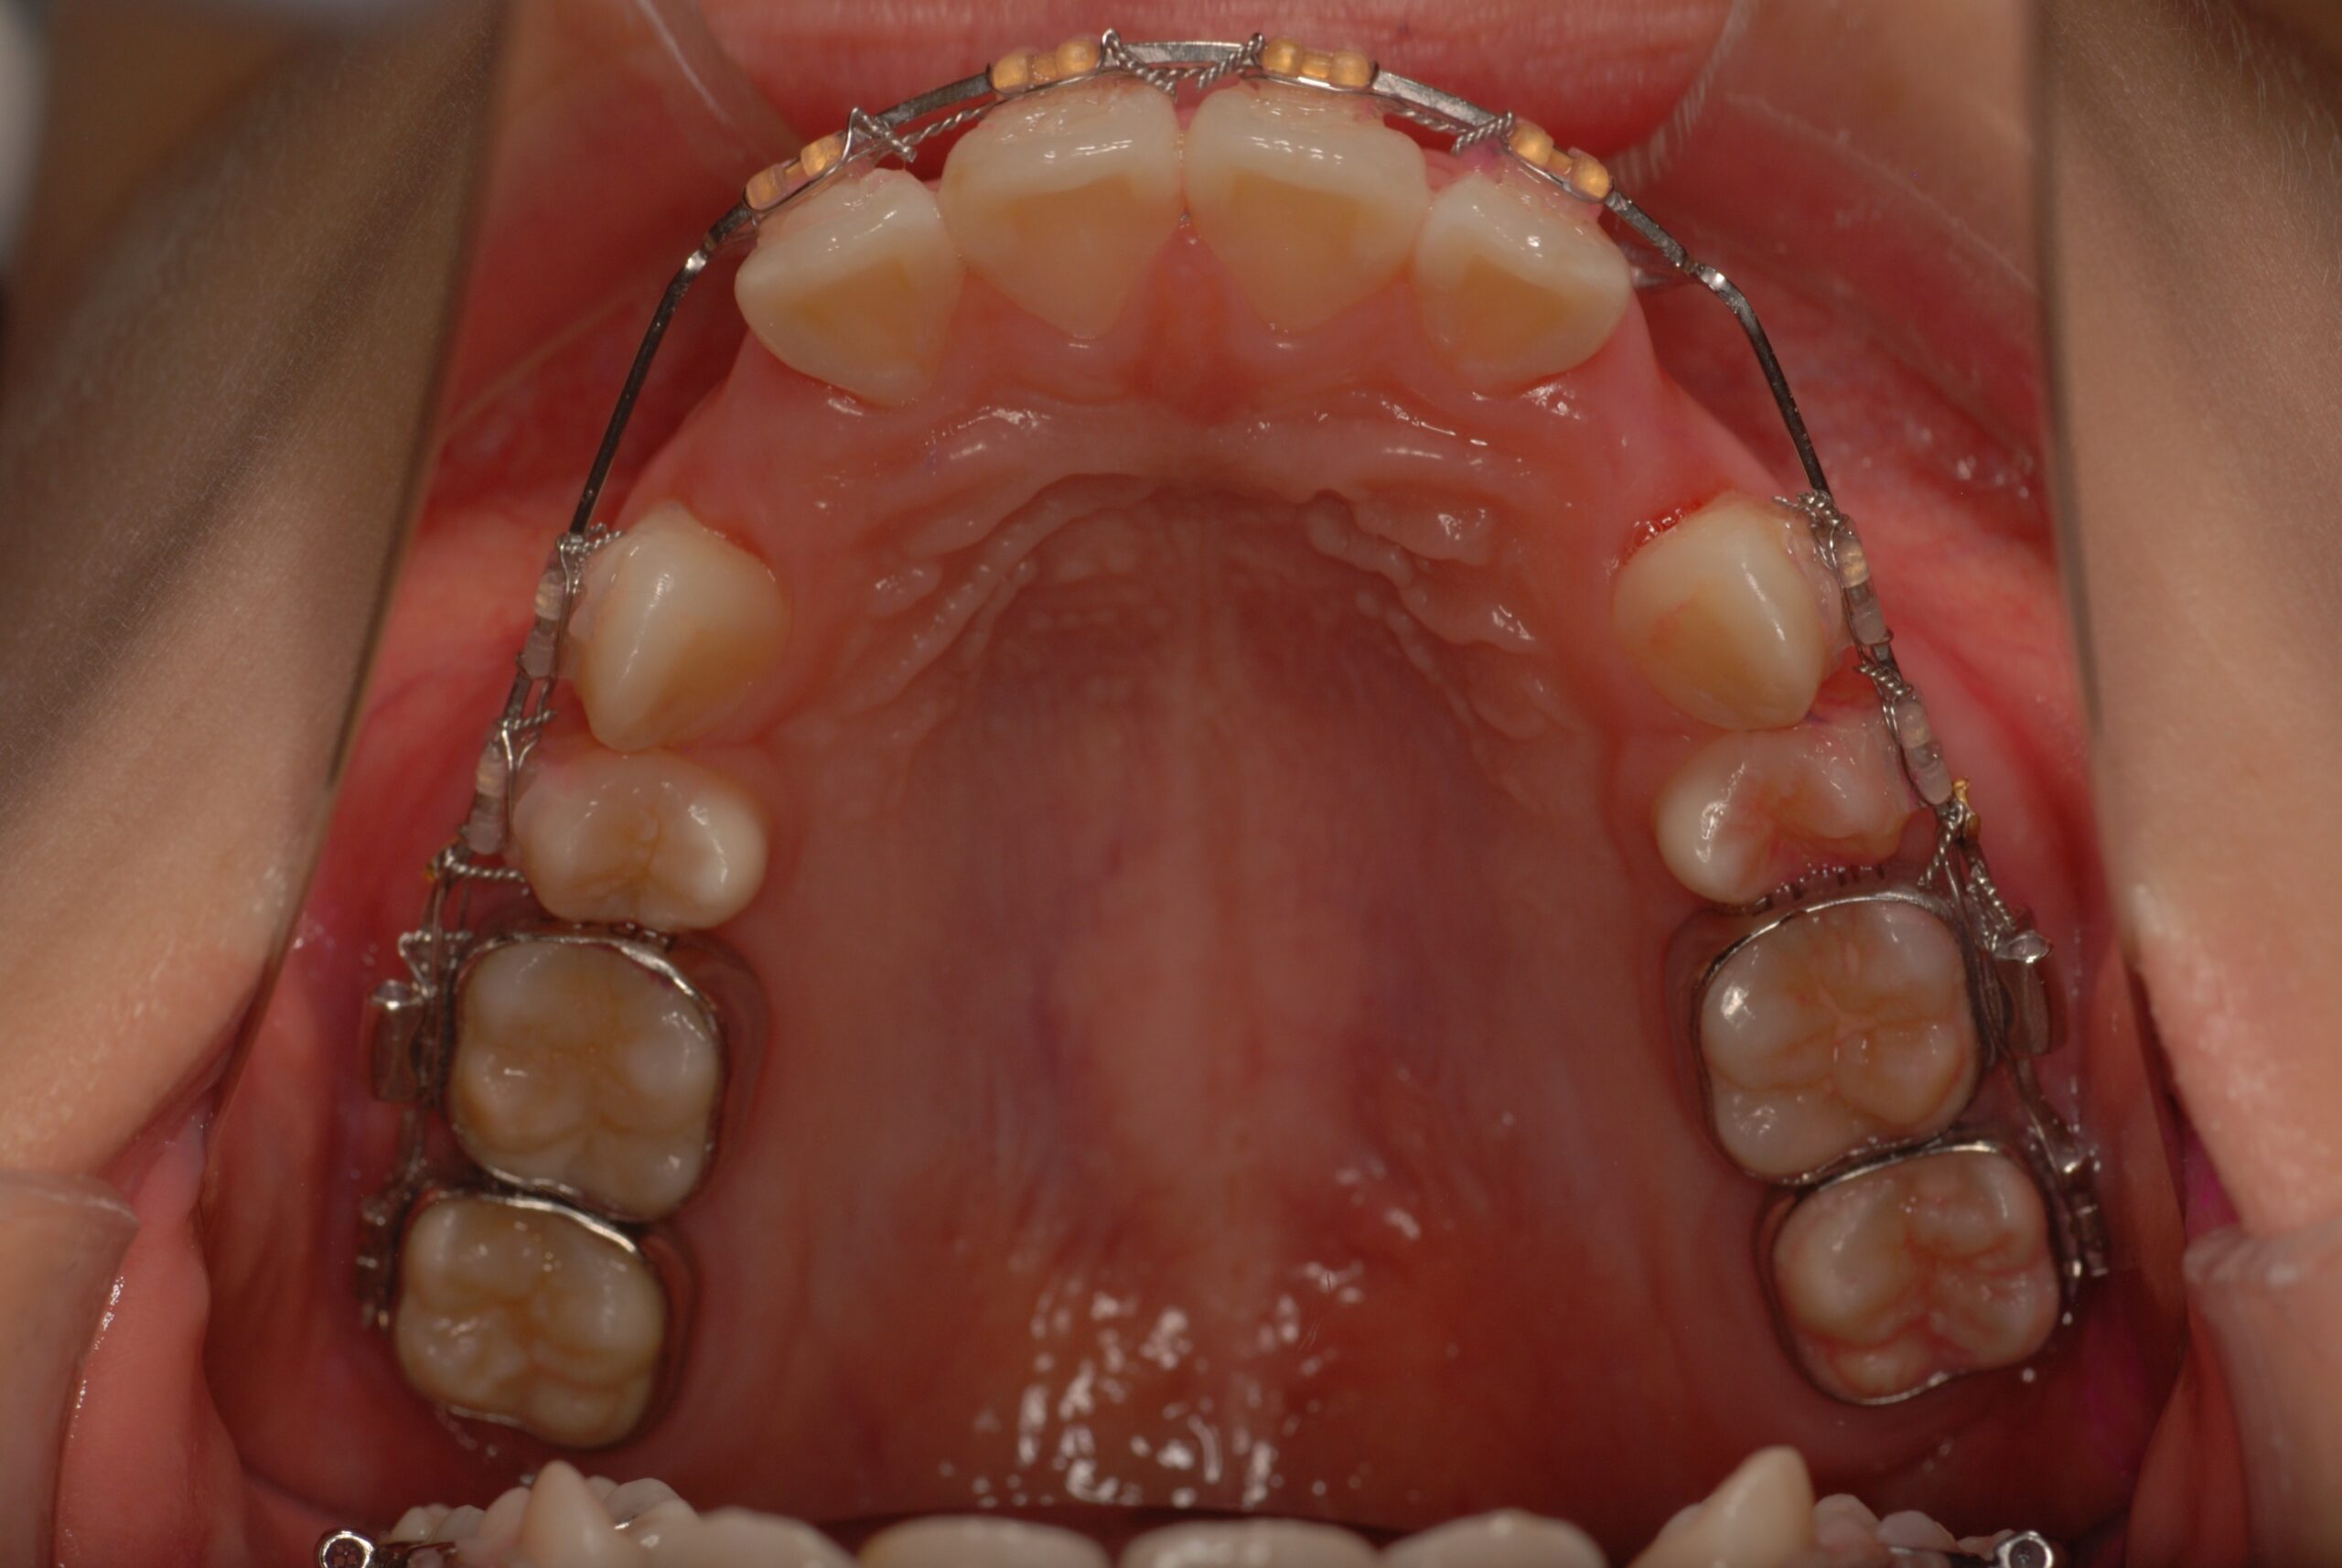

Progress

- 上顎前突、叢生。 上下顎第一小臼歯を抜歯し、抜歯空隙を利用し、顎外固定装置としてヘッドギヤを併用しながら、上顎前歯を可及的に後退させる。